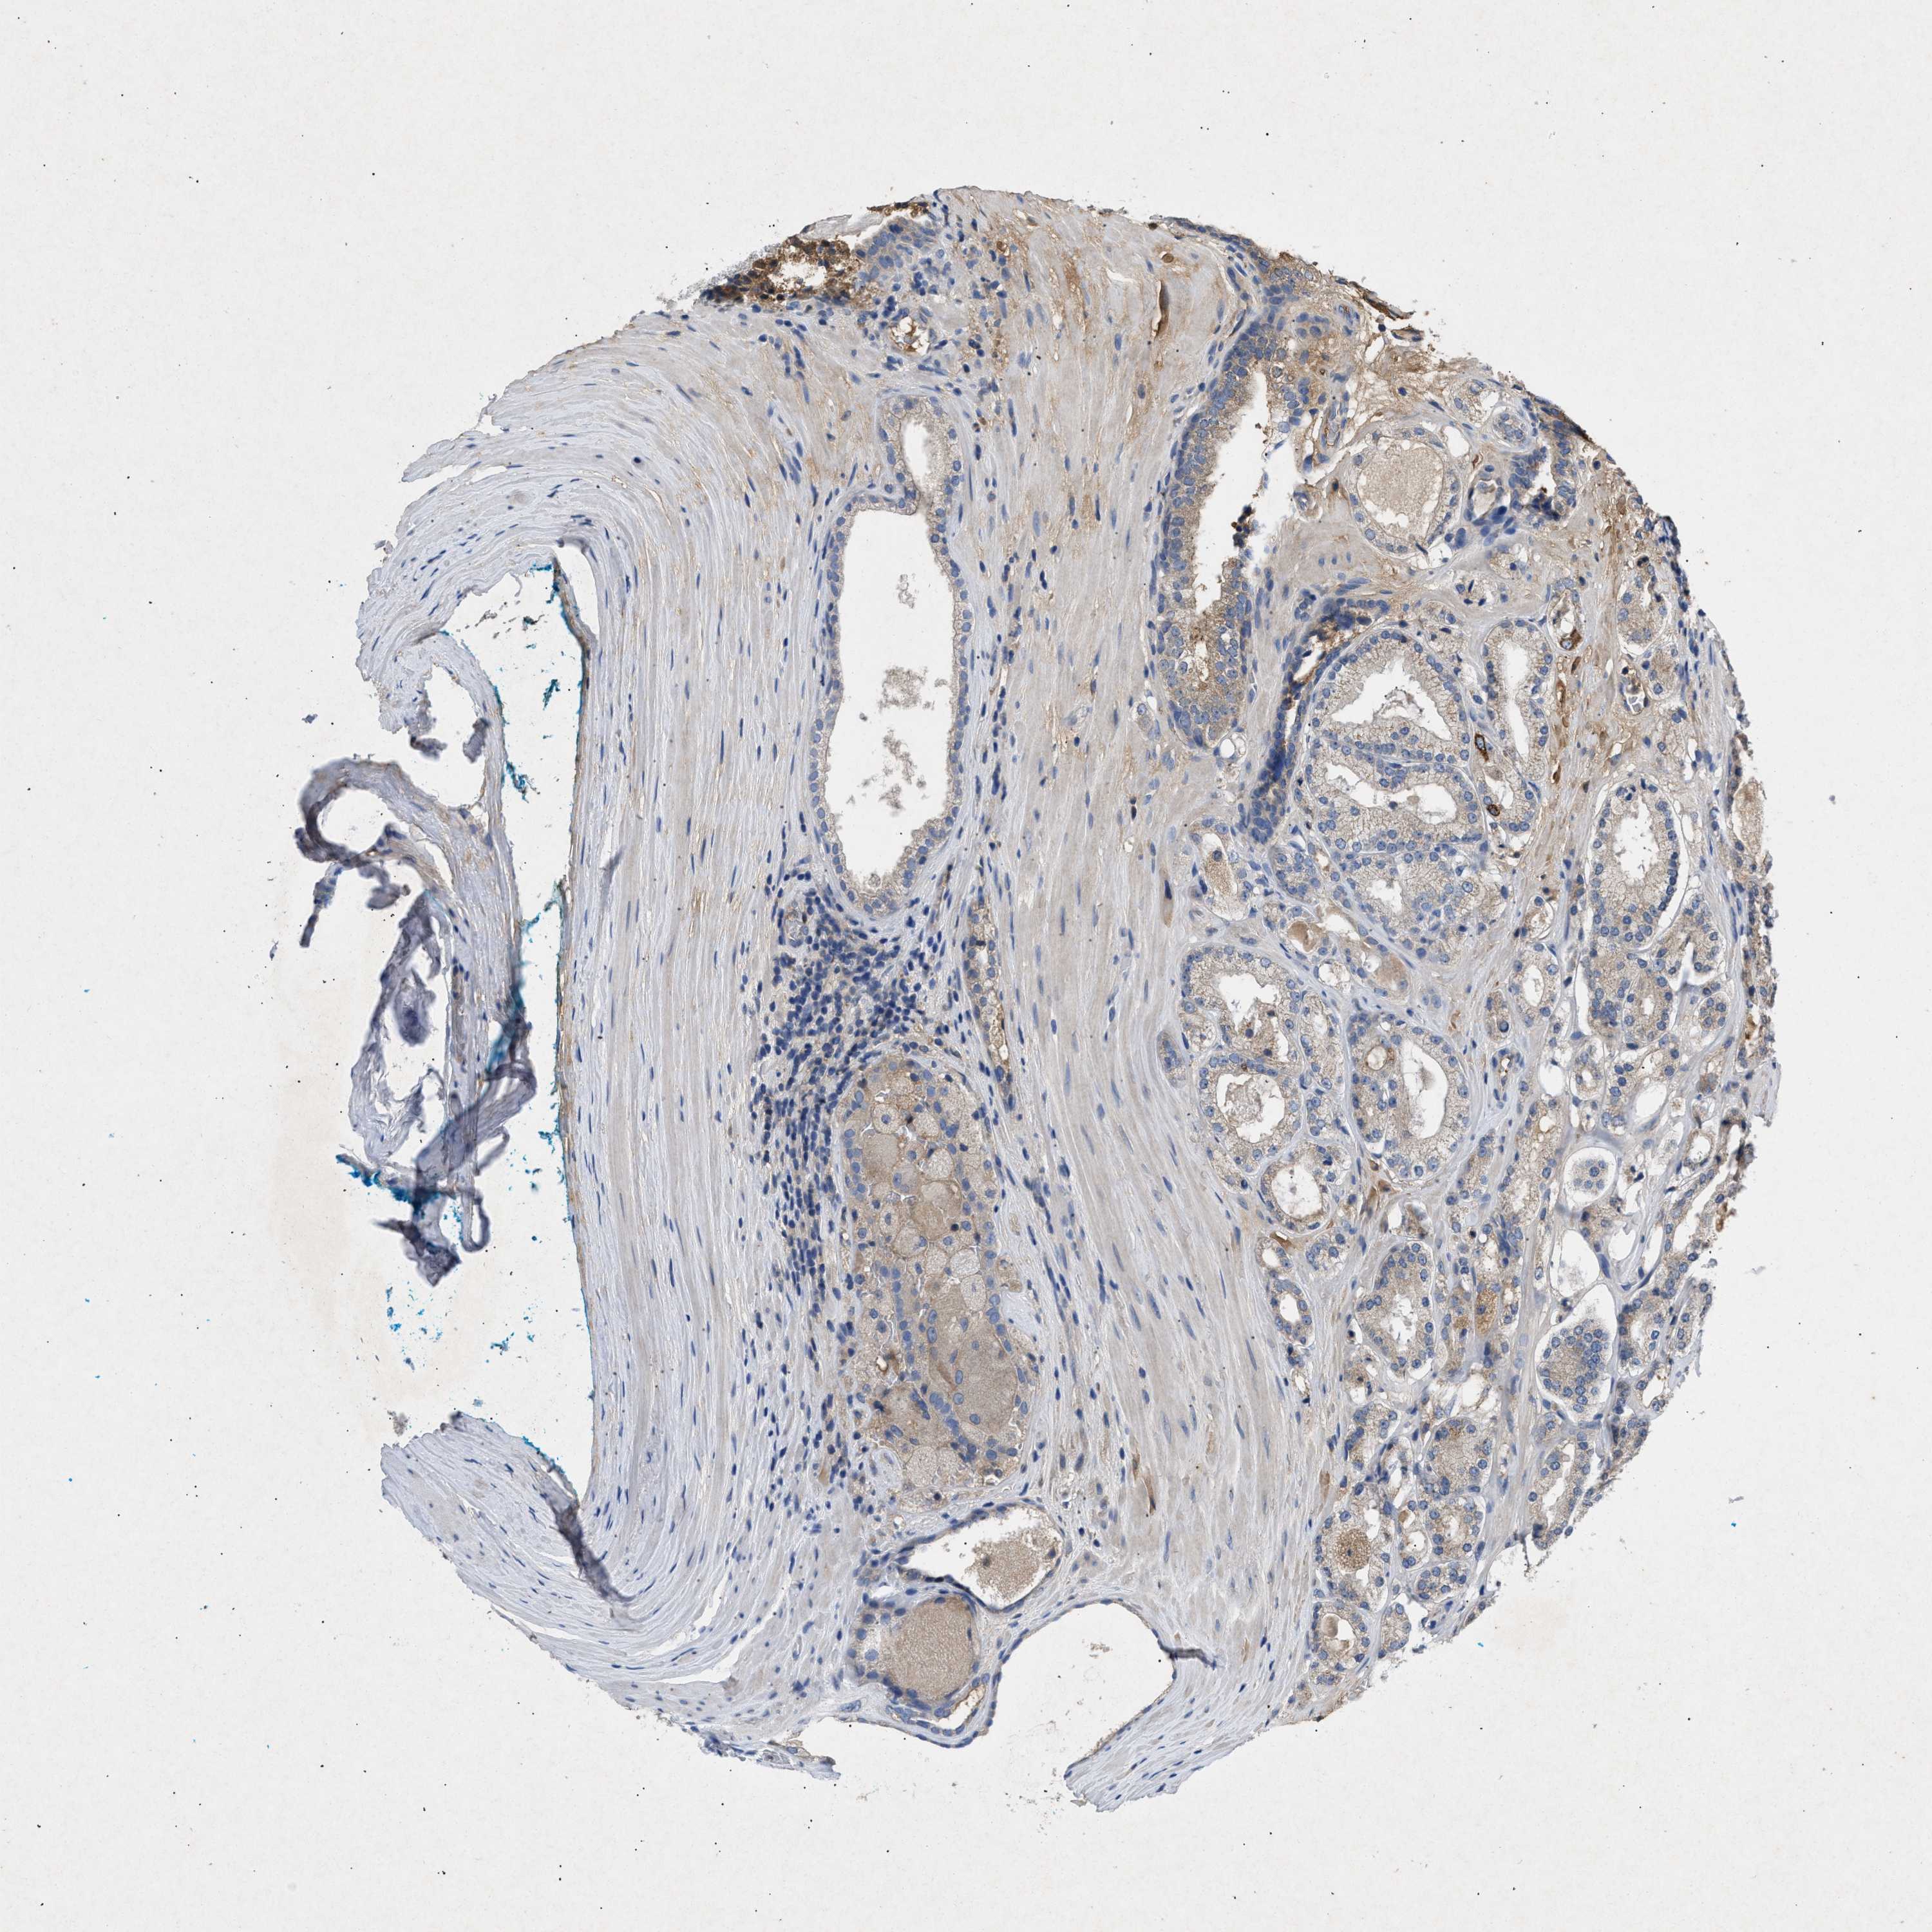

PROSTATE CANCER - Protein expressioni

A mouse-over function shows sample information and annotation data. Click on an image to view it in a full screen mode. Samples can be filtered based on level of antibody staining by selecting one or several of the following categories: high, medium, low and not detected. The assay and annotation is described here.

Note that samples used for immunohistochemistry by the Human Protein Atlas do not correspond to samples in the TCGA dataset.

Antibody stainingi

Antibody staining in the annotated cell types in the current human tissue is reported as not detected, low, medium, or high, based on conventional immunohistochemistry profiling in selected tissues. This score is based on the combination of the staining intensity and fraction of stained cells.

Each image is clickable and will lead to virtual microscopy that enables deeper exploration of all samples and also displays staining intensity scores, fraction scores and subcellular localization as well as patient and tissue information for each sample.

Antibody CAB018751

Antibody CAB034411

Staining

High

Medium

Low

Not detected

Intensity

Strong

Moderate

Weak

Negative

Quantity

>75%

75%-25%

<25%

None

Location

Nuclear

Cytoplasmic/membranous

Cytoplasmic/membranous,nuclear

Adenocarcinoma, High grade

Adenocarcinoma, Low grade